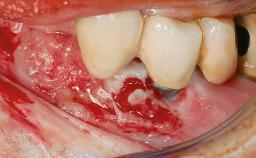

A 24-year-old female patient was treated with an implant- supported crown for single-tooth replacement at site 11. A Straumann Bone Level RC implant (Institut Straumann AG, Basel, Switzerland) was placed with simultaneous bone augmentation, and the periimplant emergence profile was conditioned with a fixed implant-supported provisional crown. After finalization of the mucosal architecture, the clinical situation was transferred by means of a custom impression post for fabrication of an implant-supported screw-retained onepiece crown consisting of a CARES® zirconia abutment (Straumann) with a direct ceramic veneer.